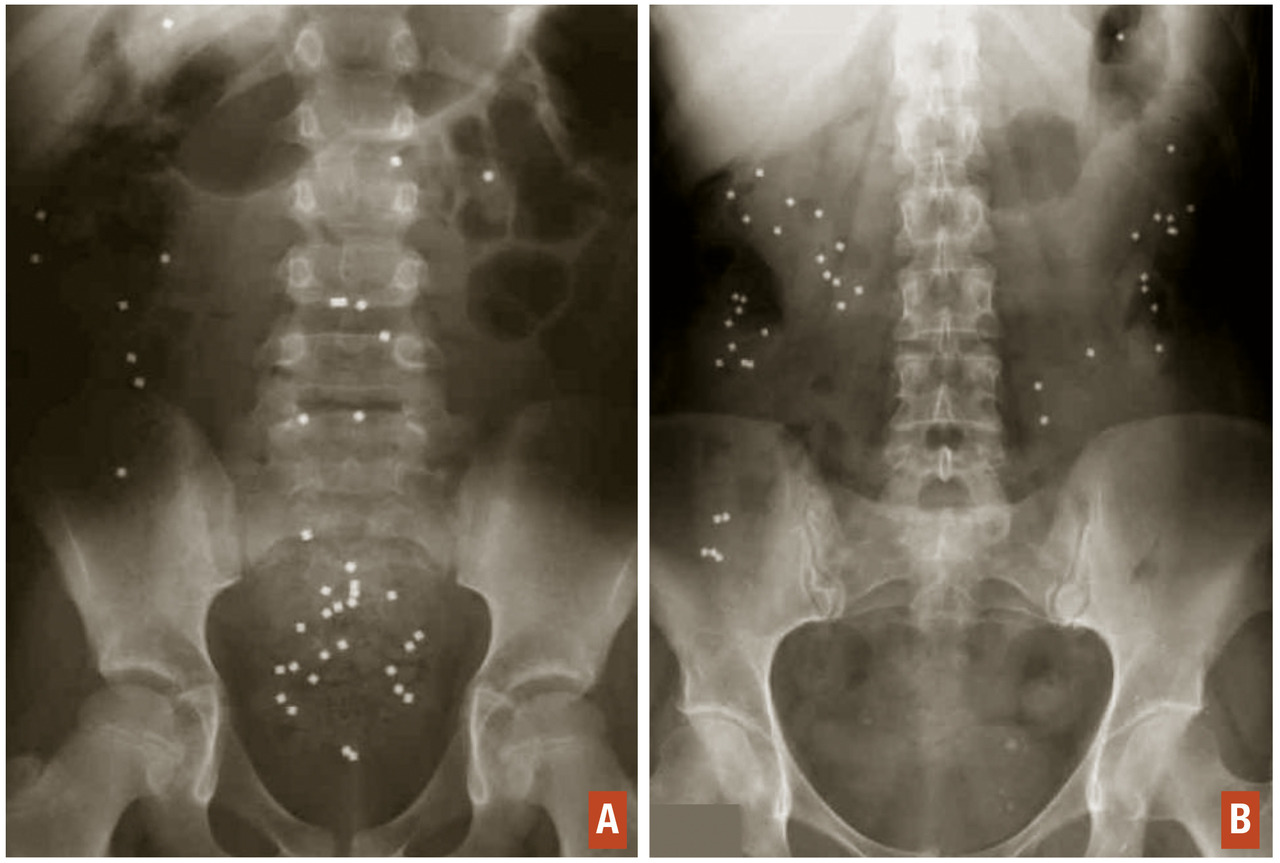

Temps de transit colique des marqueurs radio-opaques

Il s’agit d’un examen simple et reproductible permettant d’obtenir une mesure objective du temps de transit colique. Le temps de transit colique devra être réalisé sans prise concomitante de traitements laxatifs. Il consiste en l’ingestion par le patient pendant 6 jours consécutifs de marqueurs radio-opaques (10 marqueurs par jour) puis en la réalisation au 7e jour d’une radiographie de l’abdomen sans préparation. Le nombre de marqueurs résiduels présents sur le cliché d’abdomen sans préparation permettra de calculer le temps de transit, à la fois total et segmentaire (côlon droit, côlon transverse, côlon gauche et sigmoïde). Il pourra ainsi être distingué deux types de constipation, à savoir la constipation distale lorsqu’on objectivera une stagnation des marqueurs radio-­opaques au niveau du recto-sigmoïde (fig. 2A), ou la constipation dite de transit lorsque les marqueurs radio-opaques stagneront sur l’ensemble du cadre colique (fig. 2B). Le temps de transit global moyen est estimé à 67 heures en moyenne.